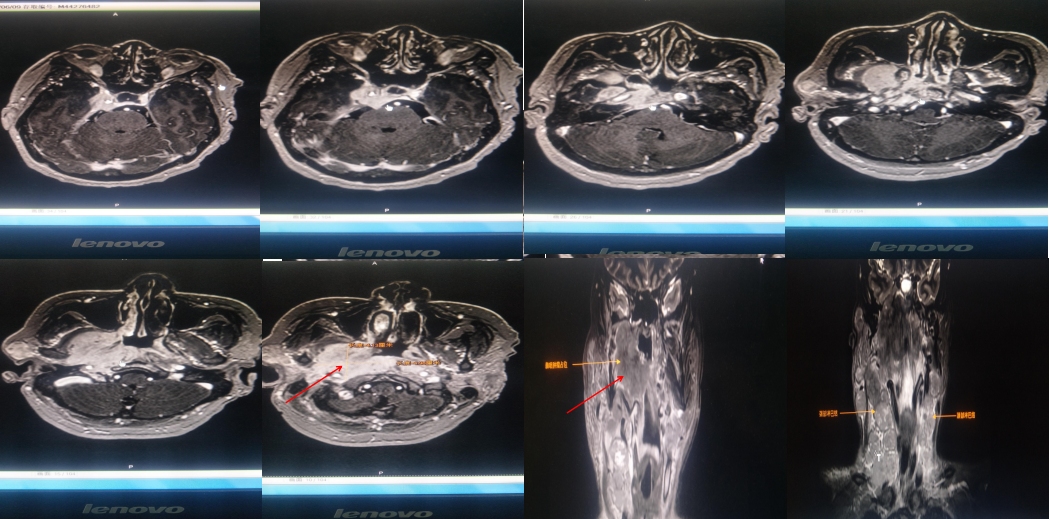

2020年6月9日我院颈部MR示:咽后壁偏右侧可见软组织影,右侧咽隐窝变窄,咽鼓管消失,病灶向外侵犯邻近软组织及颅底斜坡,包绕右侧颈内动脉,右侧翼腭窝受累,右侧腮腺受累,向左侧咽后壁延伸,颈部各区可见明显肿大淋巴结,右侧颞部脑膜受累。

横断面高信号(较白区域)为肿瘤病灶,冠状位可见明显鼻咽部肿物

2020年6月16日放疗定位,CT示右侧咽隐窝及咽后壁见巨大软组织肿块影,邻近颞骨岩部、枕髁、翼内板、翼外板、蝶窦后壁骨质破坏,双侧颌下、下颌下、耳前、耳后及颈部、右侧锁骨上、锁骨下多处淋巴结肿大。